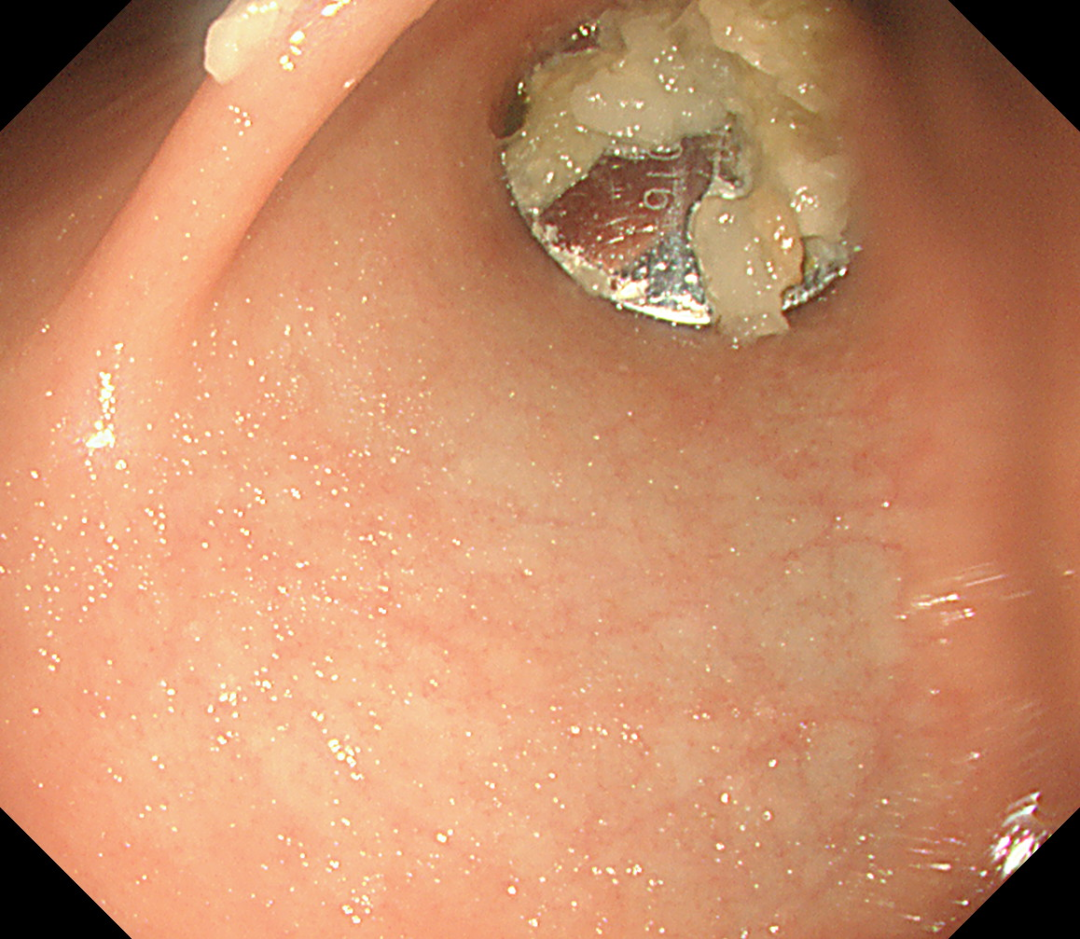

在無痛胃鏡的幫助下,手術團隊在小女孩的胃裡(lǐ)找到了那個硬币大小(直徑約1.5cm)的電池,卡在了幽門口,還(hái)好(hǎo)沒(méi)有進(jìn)入小腸。

醫生們用異物鉗小心翼翼地將(jiāng)電池取了出來,這(zhè)一刻,所有人的心都(dōu)放下了一塊大石頭。